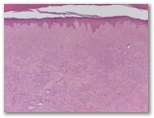

Descripcion histologica

Diagnostico